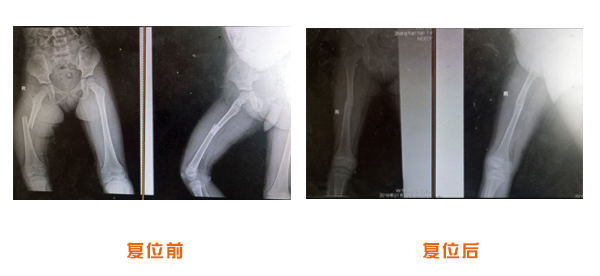

復位前后對比

肘關節脫位骨折治療前后對比

踝關節脫位骨折治療前后對比